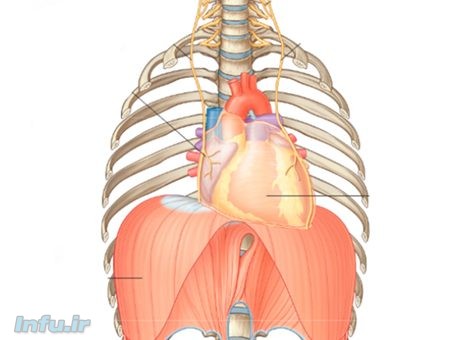

بعد از ۲۰ سالگی کمکم عملکرد ریهها ضعیفتر میشود و دیگر مثل قبل نمیتواند هوا را داخل خودش نگه دارد، اما نیازی به نگرانی نیست؛ چون شما با انجام یکسری تمرینات، موفق خواهید شد که ریهتان را تقویت کنید